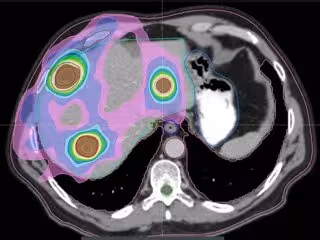

Metástasis hepáticas múltiples de cáncer de colon tratadas con SBRT.

En concreto, existen nuevas indicaciones de radioterapia como la 'Stereotactic Body Radiotherapy' (SBRT), una técnica en la que se administran dosis altas por fracción con muy elevada precisión y con una excelente tolerancia, ofreciendo cifras de control de las lesiones tratadas superiores al 80 por ciento. Al respecto, el doctor Hernando asegura que "en el cáncer colorrectal, la SBRT ha demostrado gran utilidad para el tratamiento de metástasis hepáticas y pulmonares, y ha sido avalada como una alternativa muy eficaz para pacientes con pocas metástasis que no puedan ser sometidos a cirugía o que la rechazan".